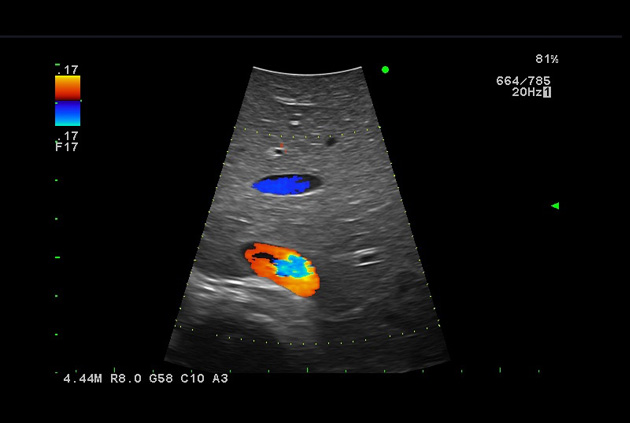

The Fujifilm Healthcare transducer utilizes the full benefits of the Wrist Articulation™ of the robotic instruments to capture real-time ultrasound imaging even at complex angles and difficult-to-reach areas.

The next level in Robotic Ultrasound

Full wrist articulation with optimized functional length.

A critical function of robotic ultrasound guidance is tumor margin identification. Fujifilm's family of robotic probes all have the optimum location of the attaching mechanism that allows for full wrist articulation of the probe. The result is an increased confidence that the tumor margins have been completely identified.